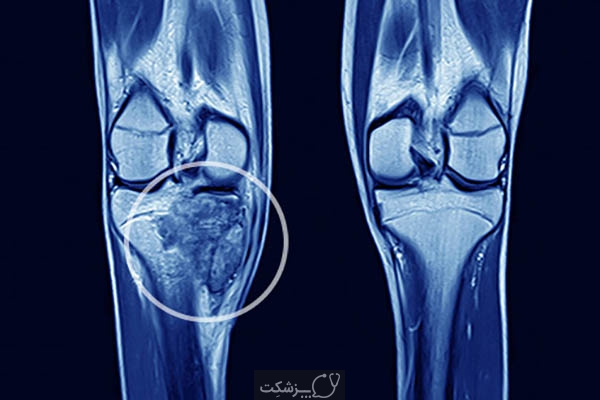

روش های عکس برداری می توانند به تعیین محل و اندازه ی تومورهای استخوان و گسترش یا عدم گسترش آن ها به سایر نقاط بدن کمک کنند. در این مقاله با علائم سرطان مغز استخوان و نیز روش های درمان آن آشنا می شوید. یک تومور رشد غیر طبیعی بافت در بدن است. سلول های توموری توانایی تنظیم کردن ندارند بنابراین سلول های بیشتری تولید می کنند و منجر به تشکیل یک توده می شوند در حالی که بسیاری از تومورها سرطانی.

تشخیص سرطان استخوان. استئوسارکوم شایع ترین نوع است که بیشتر بر کودکان و نوجوانان زیر 20 سال تأثیر می گذارد. جراحی اغلب اولین انتخاب درمانی می باشد اگرچه گاهی اوقات قطع کردن عضو لازم می باشد. درمان سرطان استخوان به نوع سرطان بستگی دارد.